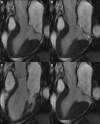

Methods and results: Thirty-six (27 female patients; median age: 44 years) arrhythmic MVP patients with LV late gadolinium enhancement on cardiac magnetic resonance and no or trivial mitral regurgitation, and 16 (6 female patients; median age: 40 years) MVP patients without LV late gadolinium enhancement were investigated by morphofunctional cardiac magnetic resonance. Mitral annulus disjunction (median: 4.8 versus 1.8 mm; P<0.001), end-systolic mitral annular diameters (median: 41.2 versus 31.5; P=0.004) and end-diastolic mitral annular diameters (median: 35.5 versus 31.5; P=0.042), prevalence of posterior systolic curling (34 [94%] versus 3 [19%]; P<0.001), and basal to mid LV wall thickness ratio >1.5 (22 [61%] versus 4 [25%]; P=0.016) were higher in MVP patients with late gadolinium enhancement than in those without. A linear correlation was found between mitral annulus disjunction and curling (R=0.85). A higher prevalence of auscultatory midsystolic click (26 [72%] versus 6 [38%]; P=0.018) was also noted. Histology of the mitral annulus showed a longer mitral annulus disjunction in 50 sudden death patients with MVP and LV fibrosis than in 20 patients without MVP (median: 3 versus 1.5 mm; P<0.001).

Conclusions: Mitral annulus disjunction is a constant feature of arrhythmic MVP with LV fibrosis. The excessive mobility of the leaflets caused by posterior systolic curling accounts for a mechanical stretch of the inferobasal wall and papillary muscles, eventually leading to myocardial hypertrophy and scarring. These mitral annulus abnormalities, together with auscultatory midsystolic click, may identify MVP patients who would need arrhythmic risk stratification.